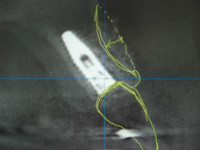

午後は右上2番(前歯)の抜歯即時インプラント埋入GBRのオペです、このオペも静脈鎮静併用下で問題なく終了いたしました。

両サイドの健全歯を削るブリッジによる治療は避けたいとの強いご意向でインプラントオペを施術させていただいた次第です。